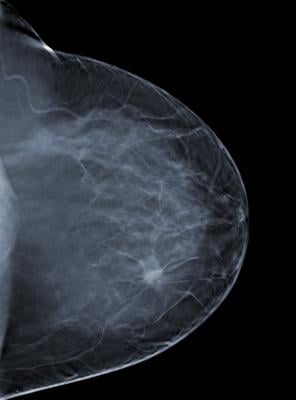

The American College of Radiology (ACR) conducted a review of mammograms performed at the facility between Sept. 8, 2014, and Nov. 4, 2014. The clinical image review was conducted for the purposes of accreditation reinstatement following the Aug. 31, 2010, ACR revocation of the facility’s accreditation. On Sept. 8, 2014, the facility was provisionally certified to provide mammography services; however, a subsequent ACR clinical image review indicated problems with the quality of the mammography at the facility. The ACR revoked the facility's application for accreditation effective Feb. 20, 2015, and the FDA suspended the facility’s certificate on March 6, 2015.

Under the MQSA of 1992, the FDA requires that all mammography facilities meet certain baseline quality standards and be certified to legally operate in the United States. This facility did not meet standards for mammography quality under the Act. The facility may not legally perform mammography at this time due to the suspension of its certificate.

This does not mean that the results of the mammograms were inaccurate, but it does mean that the patients should consider having their mammograms re-evaluated at an MQSA-certified facility to determine if the patients need a repeat mammogram or additional medical follow-up.